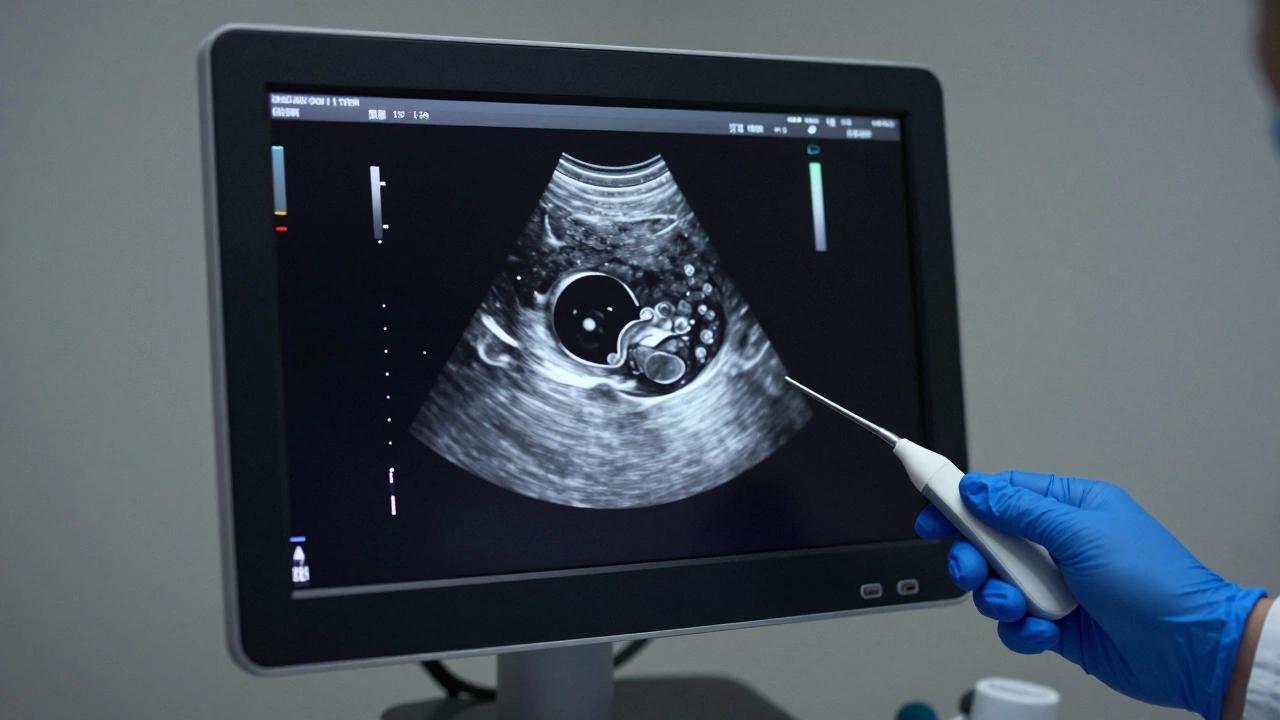

Экран аппарата УЗИ с изображением типичной кисты в виде черной полости с четкими границами

Самый первый и доступный метод - УЗИ ультразвуковое исследование, использующее высокочастотные звуковые волны для создания изображения органов. Это идеальный инструмент для поиска кист. Почему? Потому что ультразвук отлично видит разницу между плотной тканью и жидкостью. Жидкость в кисте на экране монитора обычно выглядит черной (анэхогенной). Если врач видит четкие границы и отсутствие перегородок внутри, он с высокой долей уверенности говорит: «Это киста».